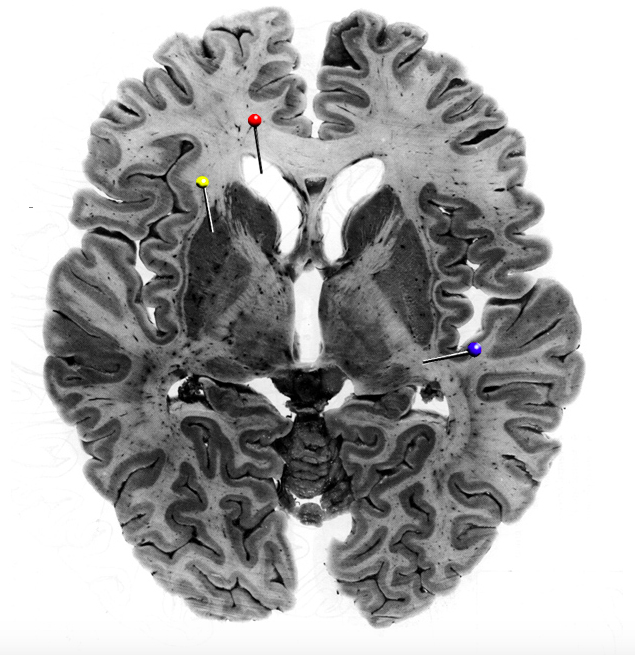

In this horizontal brain slice, the yellow pin is in

What is the structure indicated by the black pin?

What fibres is the structure marked by the black pin made up of?

Commisural fibres

In this horizontal brain slice, the yellow pin is in the…

putamen